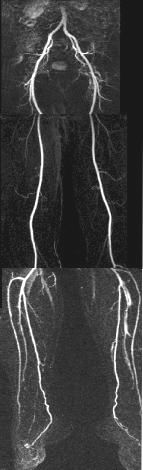

EXAMPLE:  The example shown here is on our volunteer Dr. Udkoff, who is fortunately asymptomatic and demonstrates a normal scan.  As you can see, the aorta and iliac, femoral, and popliteal arteries and trifurcations through the calf arteries all the way into the feet are exquisitely depicted.  These images are comparable to image quality of conventional x-ray angiography. In fact, the calf arteries are generally depicted better than x-ray angiography.

CONCLUSION:  Compared to conventional x-ray angiography, MRA run-off is a relatively non-invasive examination of the aorta and extremities (thanks to intravenous injection instead of transarterial catheterization, and use of gadolinium instead of iodinated contrast).  With the introduction of stepping-table technology, MRA run-off is comparable to, if not better than, conventional angiography in terms of ease and diagnostic capabilities.  The beauty of MRA is that 4D images can be rotated in every which way, a feature not possible with conventional angiography in which additional views require additional injection of iodine contrast, a potential hazard to the kidneys.  MRI contrast, gadolinium, is on the other hand very safe and only a total of 30-40 cc is injected.  We propose that with the availability of current moving stepping-table technology and ultrafast MR techniques, MRA run-off should be the first modality of choice for all run-off studies, unless there is a contraindication to MRI such as pacemakers.  Eventually, vascular surgeons will learn to appreciate the tremendous value of this new technology and will shift their preference from invasive x-ray angiography to non-invasive MRA run-off angiography.  Needless to say, contrast-enhanced MRA is equally valuable for evaluation of carotid and renal arteries.